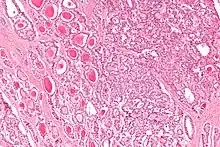

Micrograph of a strumal carcinoid. H&E stain. |

The strumal carcinoid is a type of monodermal teratoma with histomorphologic features of (1) the thyroid gland and (2) a neuroendocrine tumour (carcinoid).[1][2]